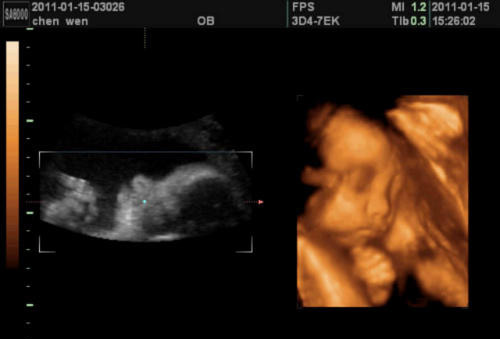

四维彩超相比传统的四维彩超,它能够观察宝宝的情况,而且图像还特别的清晰,观察的角度也是比较多的,特别的,还是动态显示的哦!通过四维彩超正确的观察,之后再通过专业医生的分析,就能够正确的判断宝宝是不是有存在畸形的地方。

为了让每一个家庭都迎接一位可爱、健康的宝宝,广州花都时代妇产医院特别采用了引进了GE四维彩超。它能够清晰显示可疑结构的立体形态、表面特征、空间位置关系,提供胎儿在宫内的立体图像,为孕期排畸检查提供了正确的科学依据。现在通过网络方式预约时代四维彩超检查,只需368元,还可享受免费获赠宝宝四维彩超的动态光碟的优惠。